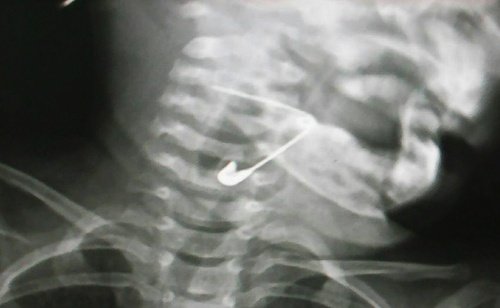

Bé 18 tháng tuổi nuốt kim băng mắc vào thanh quản

<strong>Trong lúc chơi đùa, bé gái ở Quảng Nam nuốt chiếc kim băng dài khoảng ba cm mắc trong hạ họng thanh quản.</strong><br />